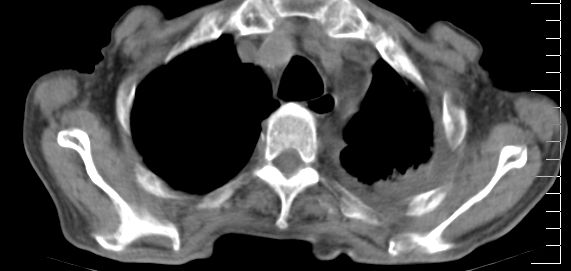

标题: CT10141:男、84岁,咳嗽、咯血1年。 [打印本页]

标题: CT10141:男、84岁,咳嗽、咯血1年。

1左侧胸腔积液并包裹2心包积液3左下肺癌?建议支纤镜检。

支持左侧中央型肺癌伴下叶肺不张\\纵隔淋巴结转移.左侧包裹性胸腔积液\\心包积液.左侧少量胸腔积液..慢性支气管炎伴部分间质纤维化.

支持:左侧中央型肺癌伴下叶肺不张\\纵隔淋巴结转移.左侧包裹性胸腔积液\\心包积液.左侧少量胸腔积液..慢性支气管炎伴部分间质纤维化.另:支气管分支根部明显阻塞 狭窄,内膜凸凹不平,提示内膜增生物。

左肺中心性肺癌并肺不张,同侧 胸膜及心包转移,左肺癌性淋巴管炎

左侧中心型肺癌,左侧胸腔积液部分包裹,心包积液,肿膈淋巴结显示。

咯血病史较长,左肺下叶实变,体积未明显缩小,隐约可见血管影及坏死阴影,双肺门及纵隔淋巴结增大,心包增厚积液,纵隔右移位,单侧胸腔积液,首先考虑:大叶型肺泡癌伴纵隔心包转移。

左下中央型肺癌伴阻塞性不张,肺炎,左侧包裹性胸腔积液\\心包积液

左肺中心性肺癌并左肺下叶肺不张,纵隔淋巴转移、同侧胸腔及心包积液(转移)。